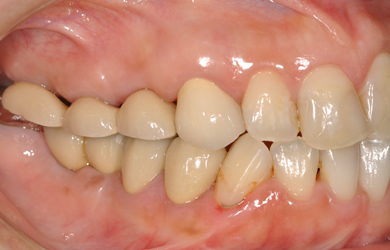

治療前

• 治療前